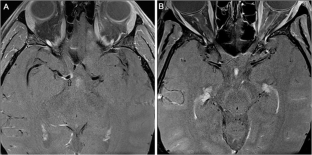

Fig. 1